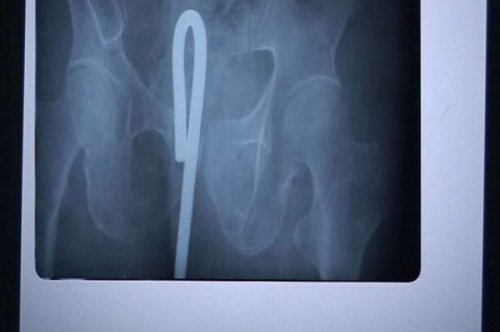

По множественным сообщениям международной прессы, 11-летний китайский школьник Лю Чеонь (Liu Cheong) столкнулся со смертью, когда его друг выстрелил ему в голову 40-сантиметровой стрелой. Стрела вошла в его череп через глазницу и застряла в голове. Каким-то чудом мальчик избежал смертельной мозговой травмы.